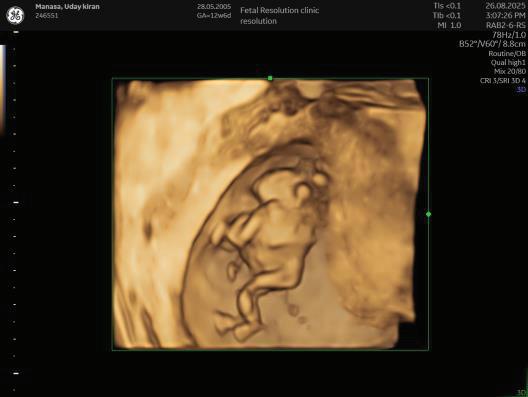

The first trimester— spanning from conception to 13+6 weeks—is no longer considered a “blind phase” of pregnancy. With the evolution of highresolution ultrasound, color Doppler and advanced biochemical screening, this period has transformed into a window of opportunity for early fetal evaluation, risk prediction and preventive strategies.

First-trimester fetal evaluation is not limited to dating the pregnancy or confirming viability—it is the foundation of predictive, preventive, and personalized obstetric care.

1. EARLY PREGNANCY SCAN (6–10 WEEKS)

Indications:

1. Confirmation of pregnancy.

2. location of pregnancy.

3. Number of fetus.

4. Cardiac activity.

5. Initial dating.

6. Assessment of uterine contour to ruleout any uterine anamolies.

7. Examnation of adenexa.

2. NUCHAL TRANSLUCENCY (NT) SCAN

• Done @11–13+6 weeks.

• CRL 45–84 mm.

• This is the cornerstone of first trimester screening.